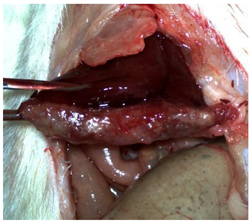

The CA + PLA patch proved effective in achieving rapid hemostasis. Upon contact with the bleeding liver, it quickly polymerized and adhered, forming a hardened, shell-like barrier that immediately stopped blood flow. Observations at PO day 50 showed that the patch remained intact on the resection plane, alongside mild to moderate abdominal adhesions. By PO day 100, while the omentum largely covered the resection site, approximately 40% of the patch had degraded. By PO day 150, peritoneal adhesions were more significant (including stomach and small bowel involvement in two instances), yet the patch itself had undergone substantial degradation, with over 80% of its original size resorbed.

For the C group, the liver resection site showed minimal scarring and adhesions, consisting mainly of omental strips attached to the resected surface.

The subjects in the T group macroscopically displayed the fibrinogen/thrombin patch present at the resection plane at all time intervals. The patch appeared to thin over time, indicating its bioresorbable nature. Notably, this group developed the fewest peritoneal adhesions.

Table 2 illustrates the appearance of the hepatic resection plane for each study group at hemostasis and on postoperative days 50, 100, and 150.